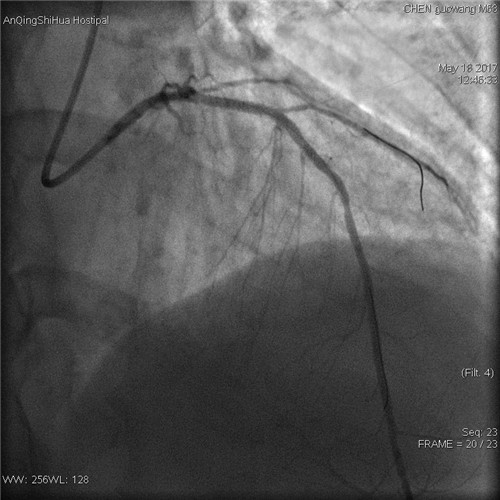

術(shù)后 前降支支架內(nèi)狹窄解除

術(shù)者先用普通預(yù)擴(kuò)張球囊預(yù)處理病變,后以與支架匹配的切割球囊于病變處擴(kuò)張,在對(duì)病變血管充分預(yù)處理后,再用藥物球囊持續(xù)擴(kuò)張。復(fù)查造影顯示,殘余狹窄<20%,血流通暢,未見(jiàn)明顯的夾層、慢血流等并發(fā)癥,“介入不植入”藥物球囊治療大獲成功。